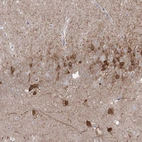

Immunohistochemical staining of human hippocampus shows strong cytoplasmic positivity in a subset of neurons.